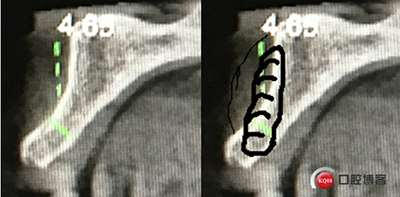

“以修復(fù)為導(dǎo)向”,在前牙種植體中心點(diǎn)就是未來牙冠舌側(cè)窩位置。那這個(gè)病例植體的方向和位置就只能是下圖右側(cè)這樣了。很明顯植體根尖部分要穿出唇側(cè)倒凹的。怎么辦?翻大瓣植骨蓋膜減張縫合?不!可以不翻瓣,大家仔細(xì)看看下圖右圖我畫的那條細(xì)細(xì)的弧線,是不是跟原來唇側(cè)凹陷的骨面成為左右對(duì)稱的兩條弧,也就是說骨膜從原來唇側(cè)凹陷骨面上剝離然后放到左側(cè)我畫的那條弧線那里根本不需要減張,這兩條弧線之間也就是唇側(cè)凹陷處放上骨粉,骨膜不會(huì)增加張力。不知道大家看明白了沒有。